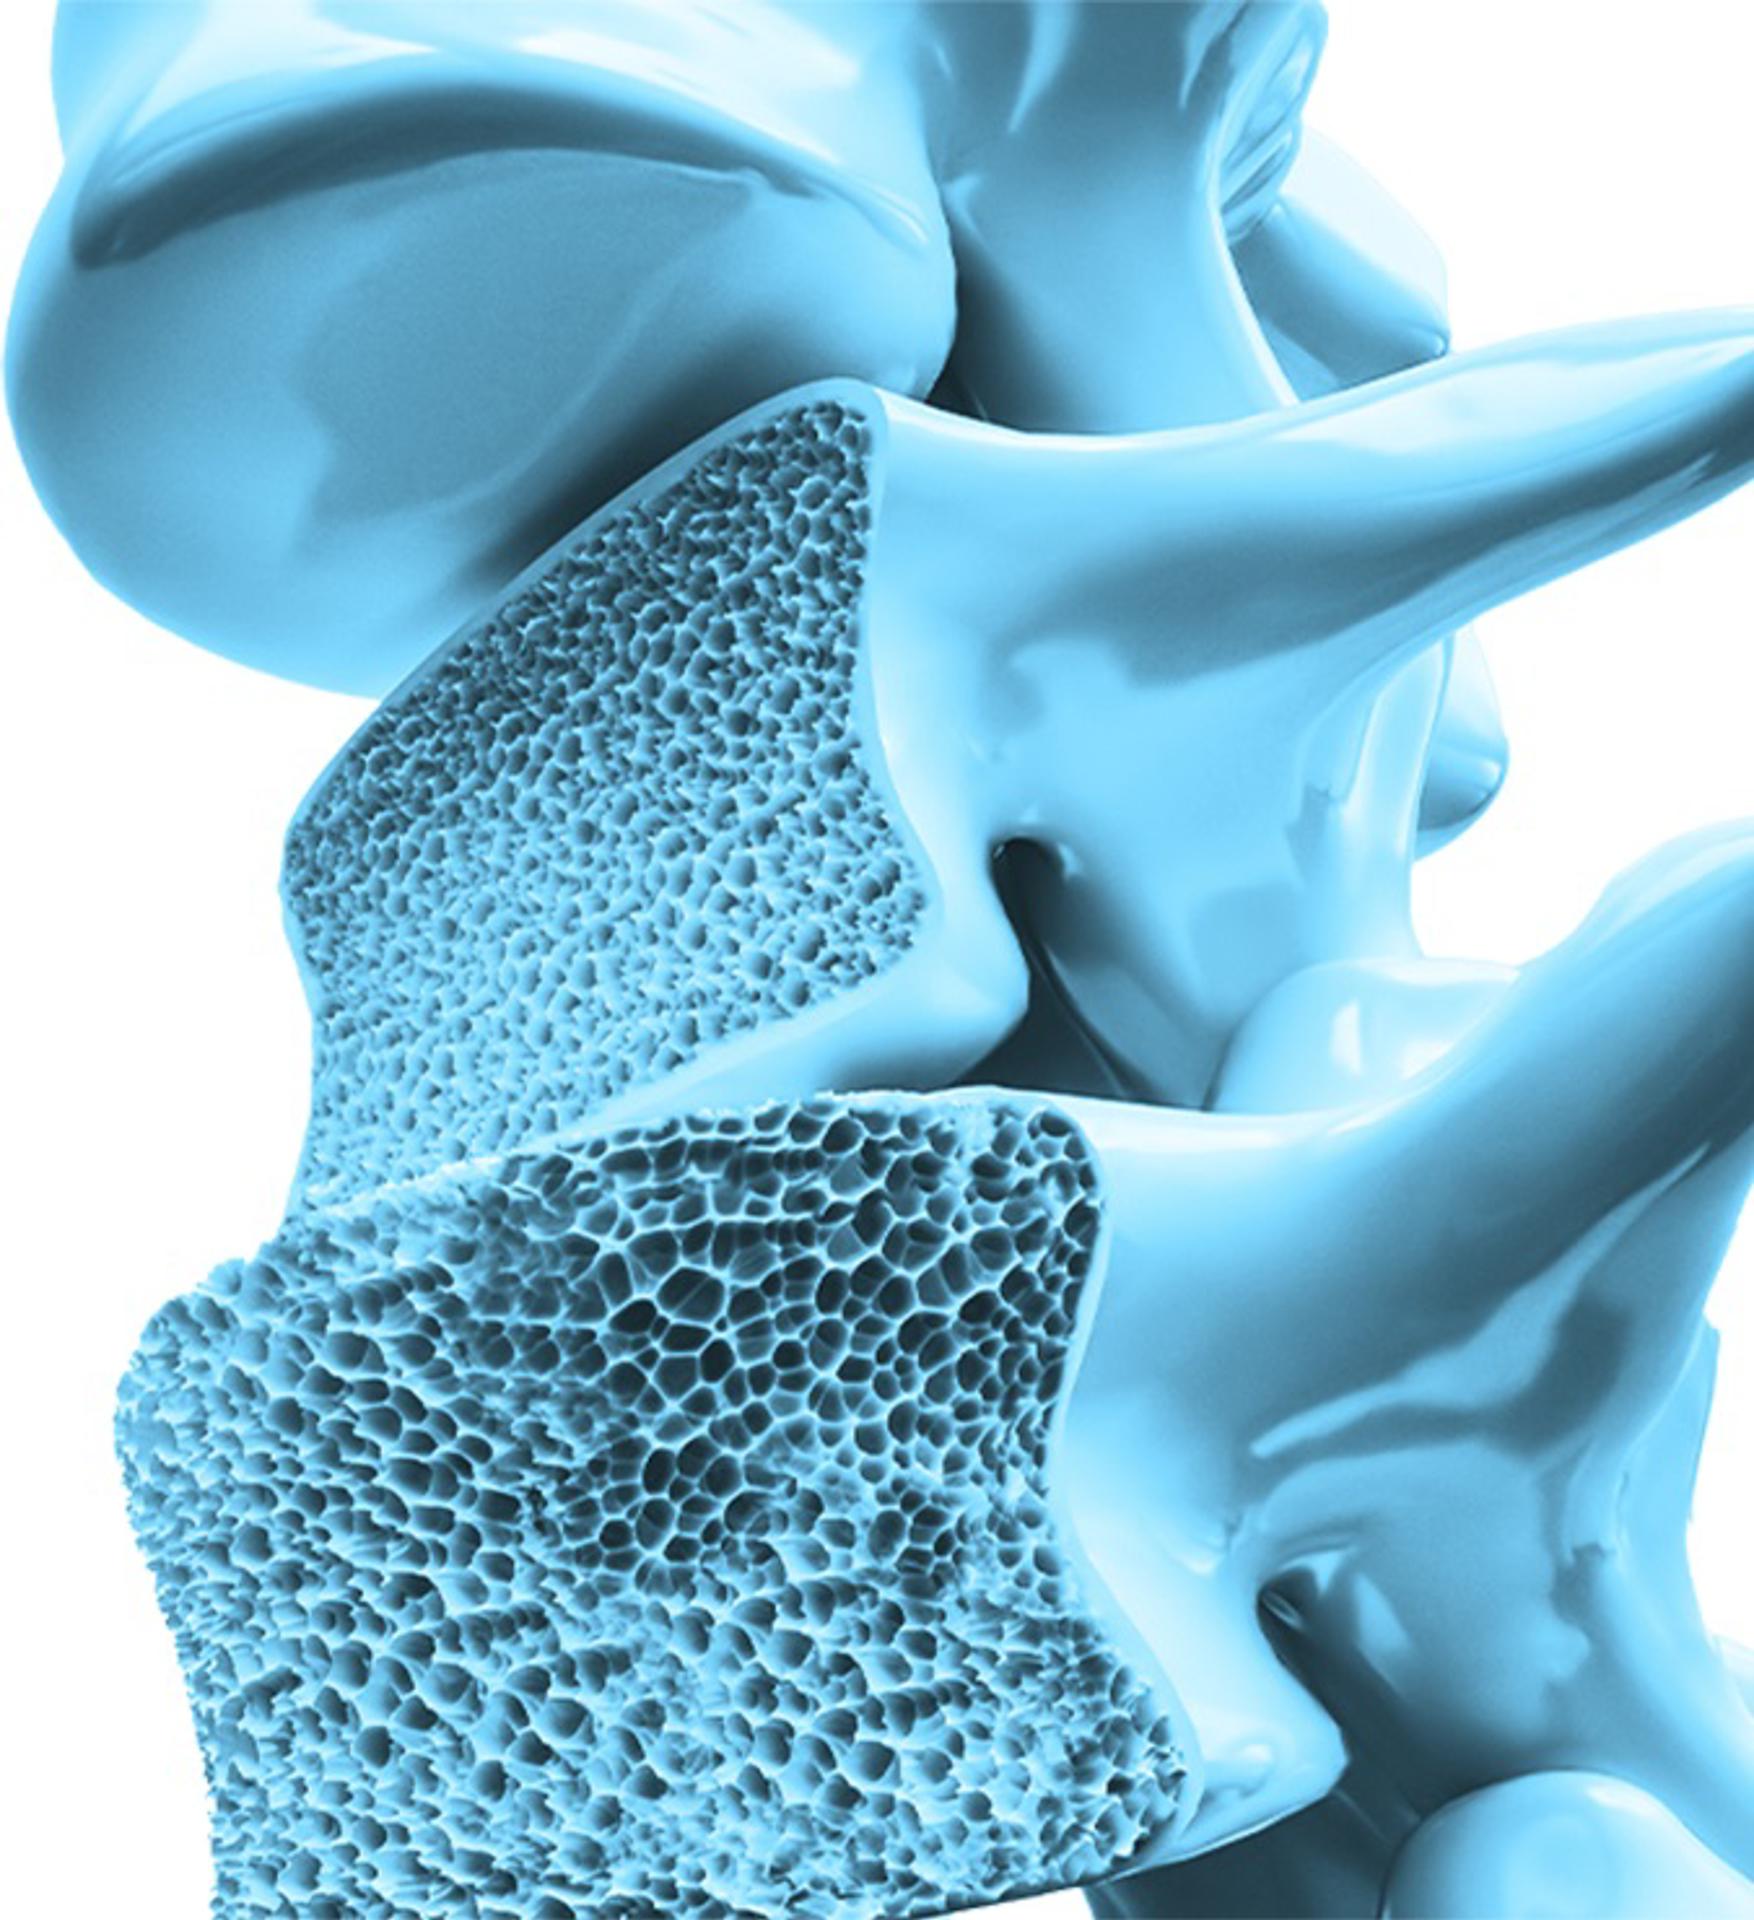

En el marco del Día Mundial de la Osteoporosis, que cada año se conmemora el 20 de octubre, Amgen, líder en biotecnología, se une a los esfuerzos mundiales de sensibilización sobre la prevención, diagnóstico y tratamiento de esta enfermedad en los huesos que es crónica, progresiva e incrementa el riesgo de fracturas.

A medida que la esperanza de vida aumenta, el envejecimiento poblacional se vuelve un factor de riesgo para padecer osteoporosis.

La disminución de los niveles de estrógeno en las mujeres durante la menopausia es uno de los principales factores de riesgo ya que el proceso de recambio óseo se acelera y, con éste, el ritmo de pérdida de hueso.

Otros factores de riesgo incluyen problemas de tiroides, desajustes hormonales, bajo consumo de calcio, uso prolongado de medicamentos corticoesteroides y antecedentes familiares de primera línea que padezcan o hayan padecido osteoporosis. Se estima que las personas con una madre, tía o hermana con osteoporosis tienen una predisposición entre 50 y 85% de desarrollar la enfermedad.